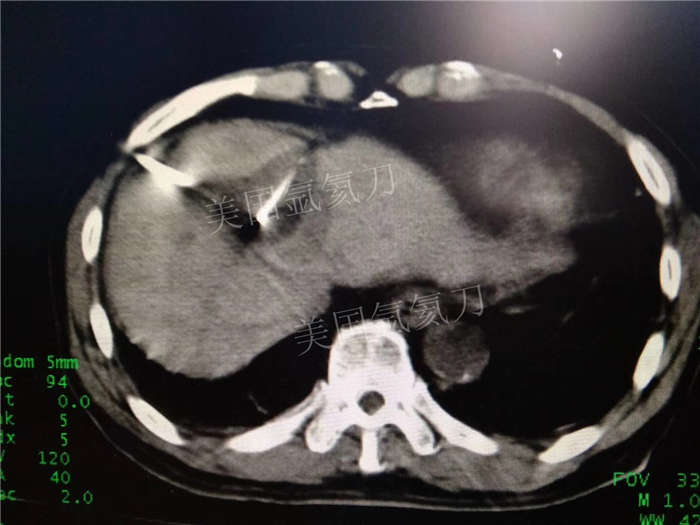

博罗人民医院乙状结肠癌术后肝转移化疗后冷冻消融